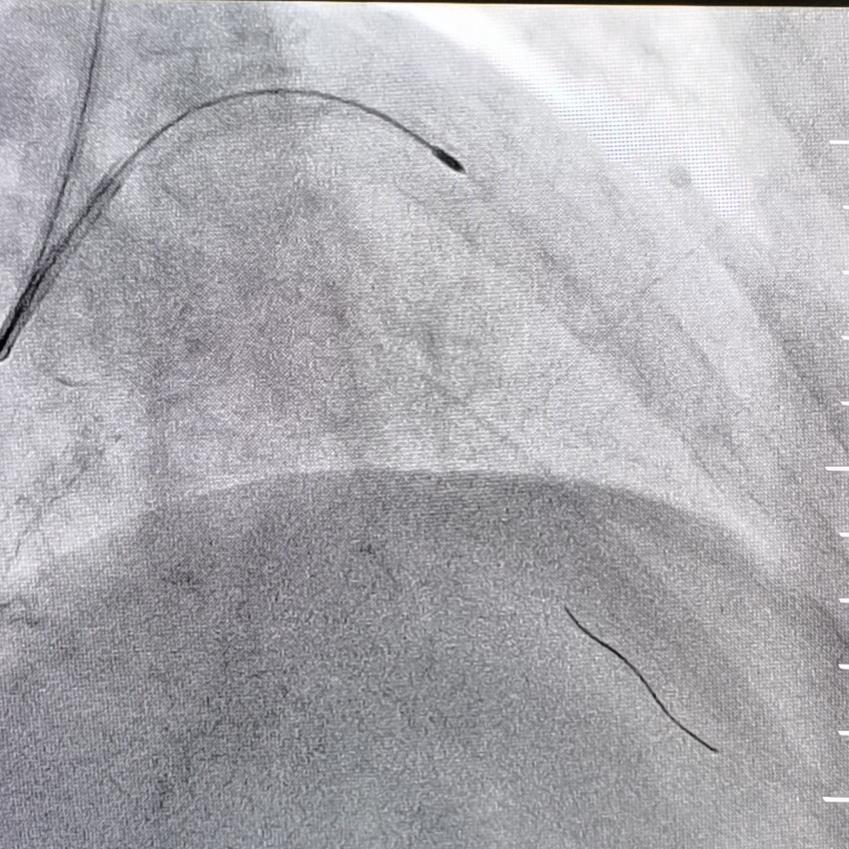

冠状动脉 旋磨

心内科二成功开展冠脉内旋磨术为冠脉严重钙化患者带来福音新技术

心血管内科一病区成功开展冠状动脉内旋磨术

冠状动脉旋磨术是采用呈橄榄型的带有钻石颗粒旋磨头,根据差异切割及

旋磨术主要适用于解剖学上高危的病变,如钙化的病灶,开口处病灶,球囊